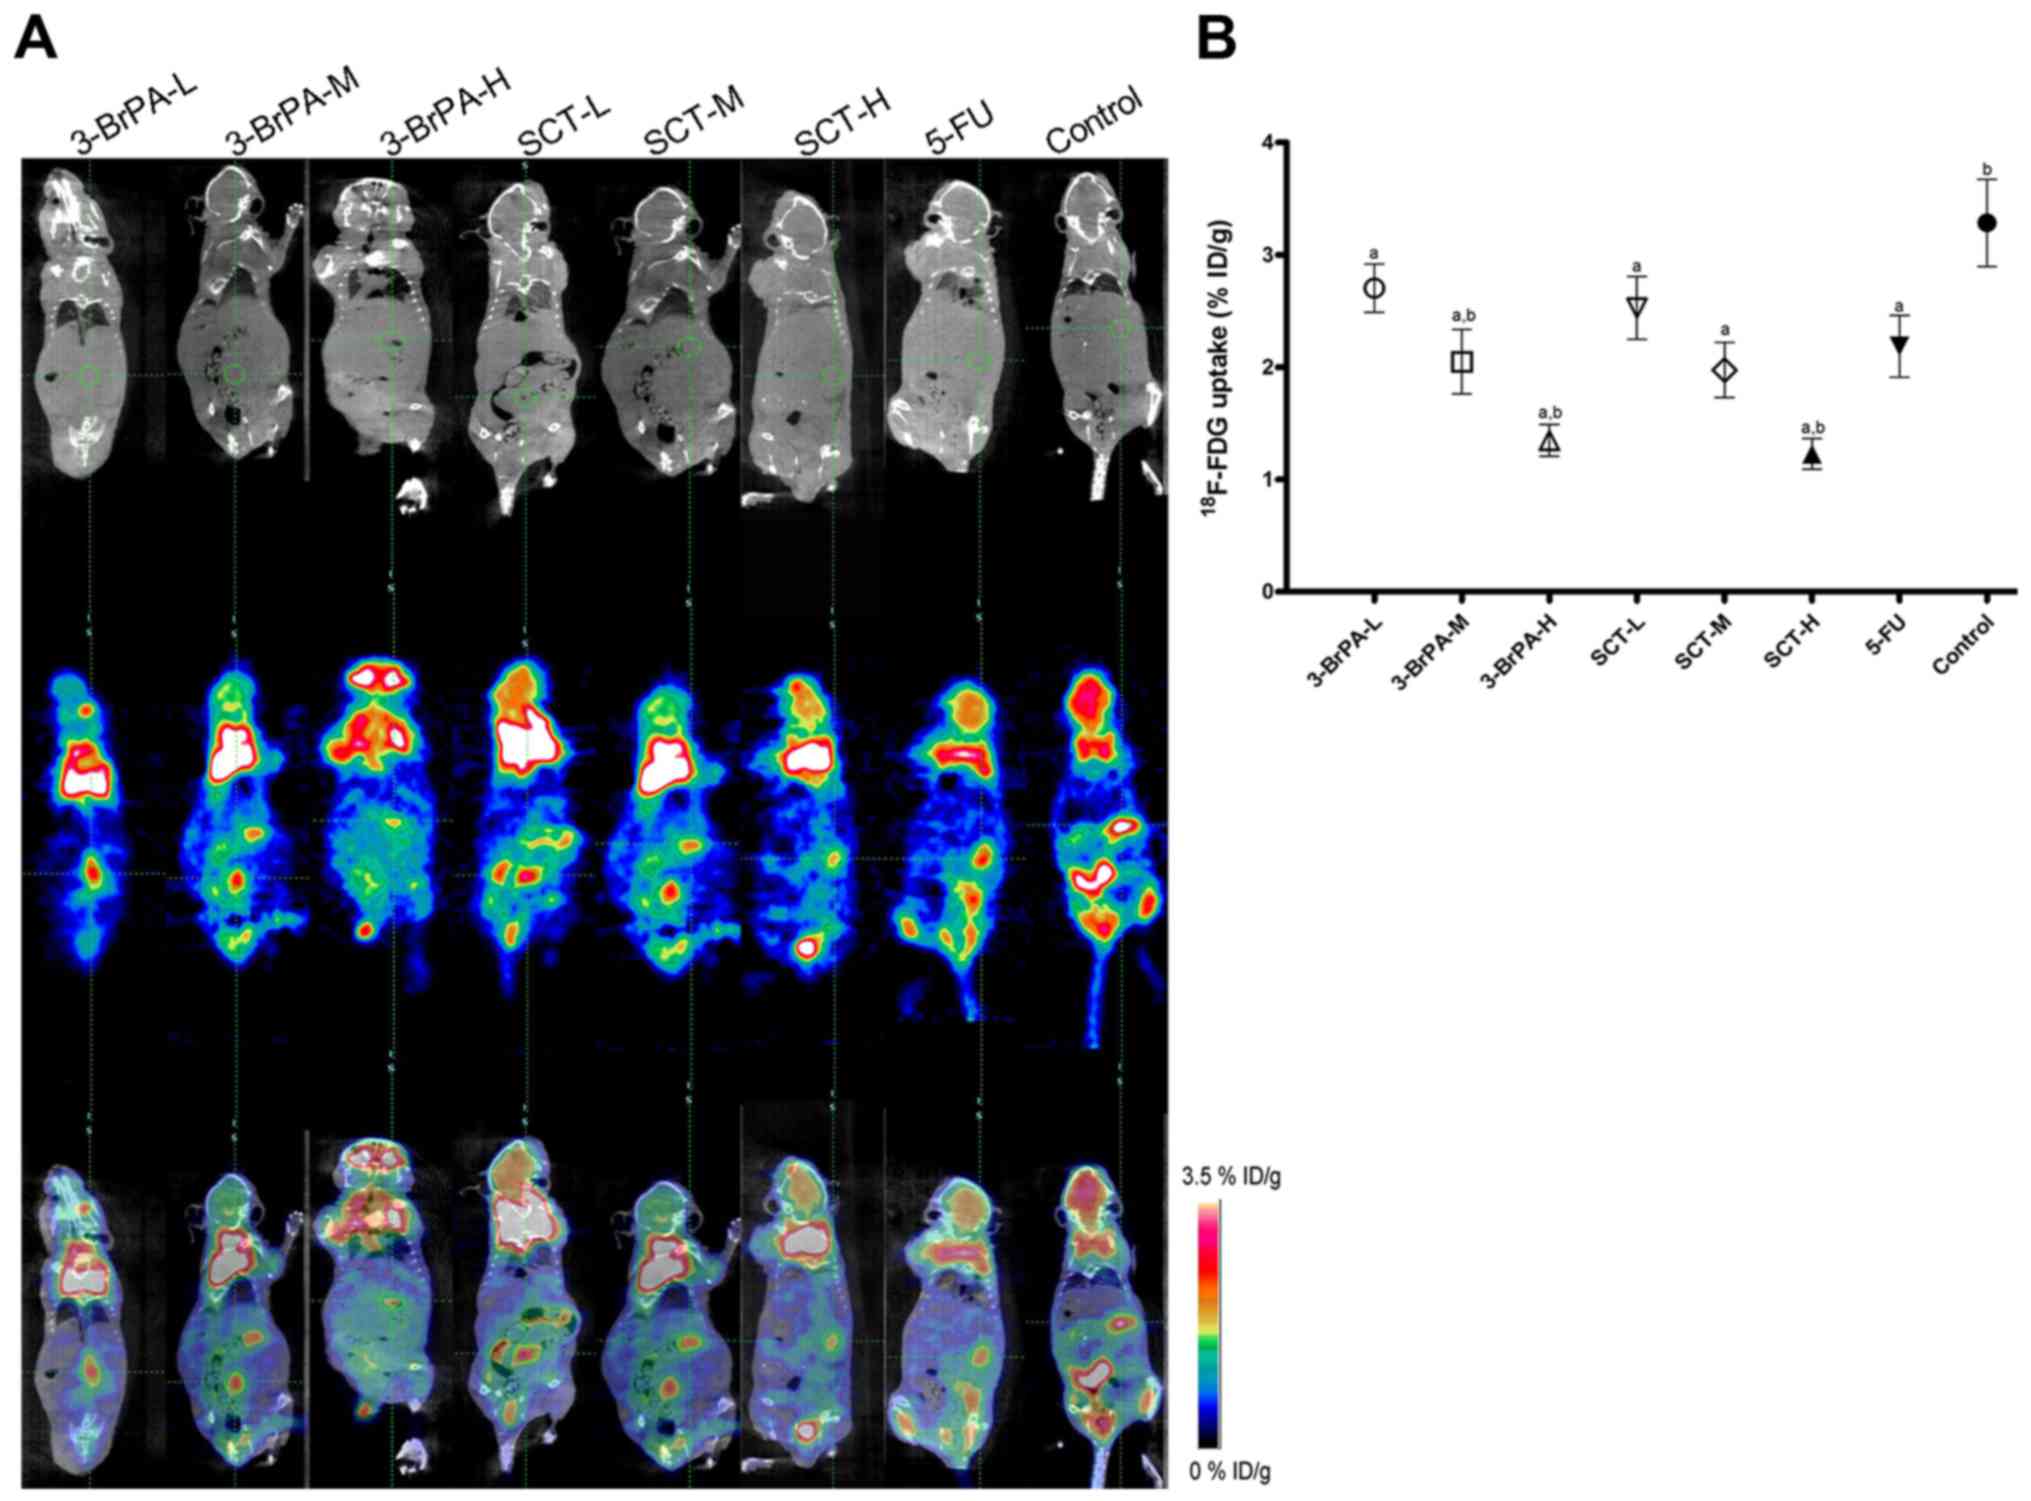

Total Body 18F FDG PET CT Imaging A Tool For Diagnosis And Quantifying

Combined 18F FDG PET CT Imaging And A Gastric Orthotopic Xenograft